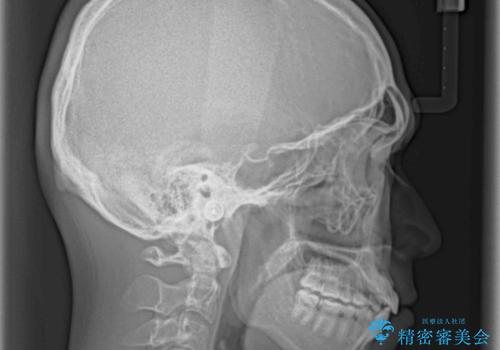

- 前歯のデコボコと若干口元が突出していることを気にして来院された患者様です。

全体的に軽微な叢生が認められ、口元もやや前方に突出していたため、インビザラインでのIPR(歯と歯の間を削る)と歯列全体の後方移動によって歯並びを整えることとしました。

上下ともに歯列の幅が狭かったため、側方に拡大することで前歯のデコボコや突出感を解消するためのスペースを獲得することができました。